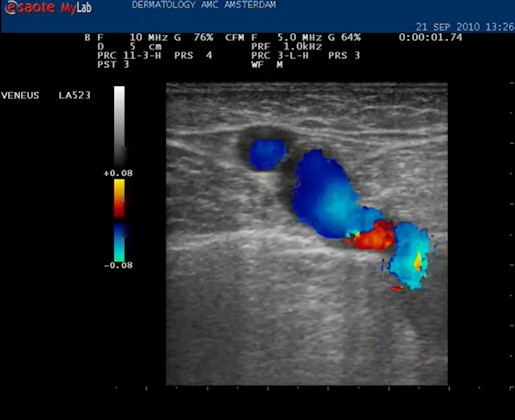

| Knijp in het been onder de echo kop. Het bloed stroomt omhoog en dat geeft een blauwe kleur (normaal) maar bij het loslaten stroomt het bloed terug en wordt het gehele vat langdurig rood. Nu weten we dat de kleppen in deze vene kapot zijn. De kleuren blauw (omhoog stromend, veneus) en rood (omlaag stromend) worden alleen goed weergegeven als de echokop goed wordt gehouden, met het pijltje omhoog. |

| Knijpen in het been: het vat wordt geheel rood bij loslaten: de vena saphena magna is insufficiënt. |